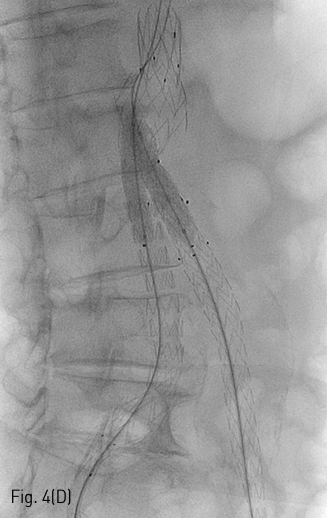

(C,D) Spot radiography shows introducing stent by kissing method.

Fig 4D

이후 우측 경로를 이용하여 AngioJet 기구를 진입시켜 2-3회에 걸쳐 혈전용해술을 시행하였고 우측 장골 분지의 내경은 회복되었다 (Fig. 4B). 이후 양측 경로에 들어있는 유도철사 (Terumo, Tokyo, Japan) 를 5Fr Berenstein catheter (Cordis, Milpitas, US) 를이용하여 Lunderquist (COOK medical, Søborg, Denmark) 유도철사로 교환한 뒤, Express LD premounted (Boston scientific, Boston, US) 스텐트를 우측은 8x37mm, 좌측은 10x37mm로 선택하여 꺽인 부위에 진입시켰다(Fig. 4C). 양측에서 조심스럽게 실시간으로 관찰하며 균형을 맞추어 스텐트를 설치하였다 (Fig. 4D). Mustang (Boston scientific, Boston, US) 9x60mm 크기의 풍선을 이용하여 설치 후 풍선확장술을 시행하여 최종적으로 스텐트의 모양을 완성하였다(Fig. 4E). 시술 직후 시행한 최종 혈관조영술 상에서 양측 분지로의 혈류가 정상적으로 회복되었으며, 혈류 속도도 양측이 균등함을 확인하였다(Fig. 5).